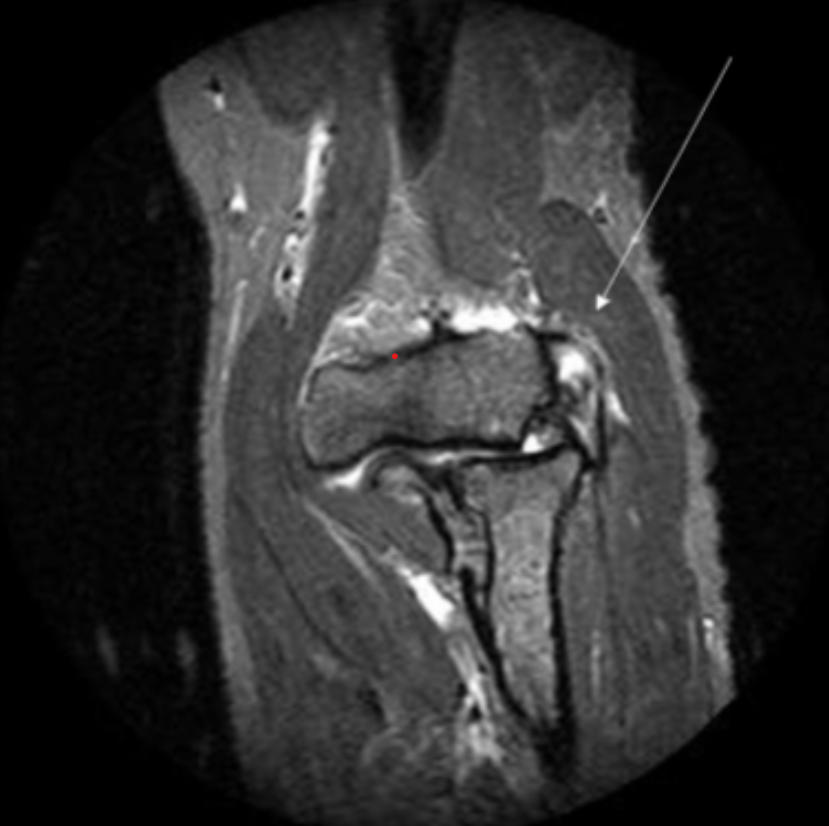

Describe the pathology indicated by the arrow (Sag PD).

ACL tear